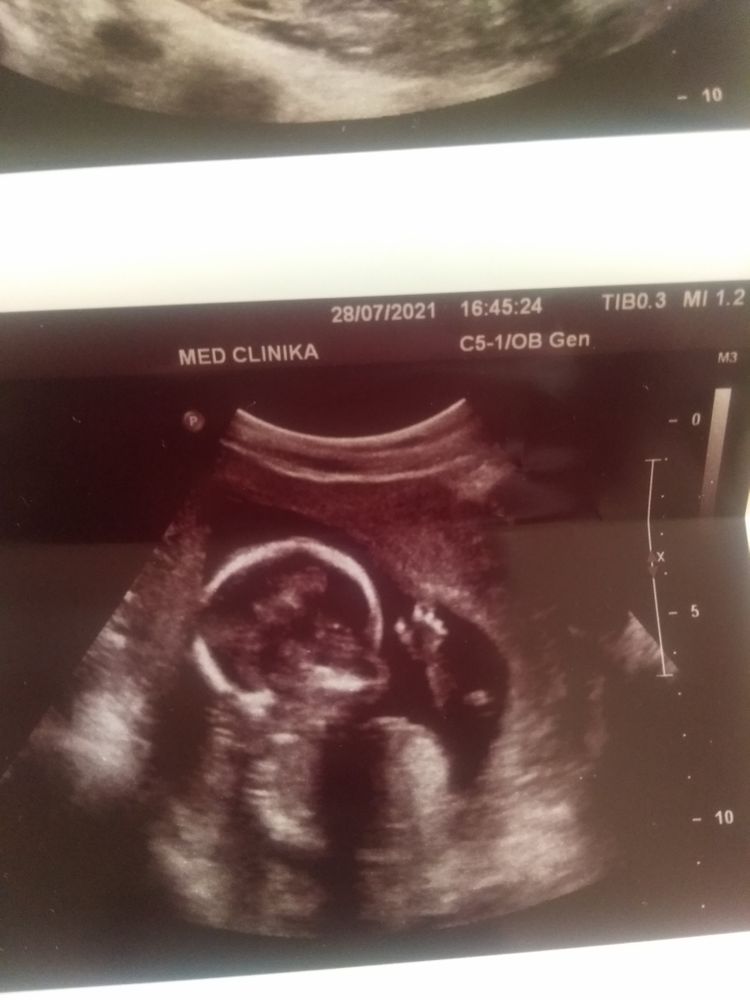

Сегодня была на узи.Срок по мд 16.0.По узи 17.2. Опережаем срок.Ну подскажите,это фото с полом?Узистка сказала мальчик будет.Вес 180гр.Третий сосуд в пуповине увидели и даже показали.Я очень рада.Зато в головке нашли какие то кисты.Узистка сказала ничего страшного,дальше котроль в 20 недель.Очень надеялась на девочку)Может еще не точно определила?! Кто знающий,помогите.

Valeriya, а это не может быть похоже на пуповину?есть хоть какой то шанс у меня?

КАРАМЕЛЬКА, ну а у основания что там такое широкое может быть? Похоже на мошонку вид снизу🤔 а потом пенис идёт.

сходите еще раз на узи, подтвердите или до 2 скрининга дотерпите.